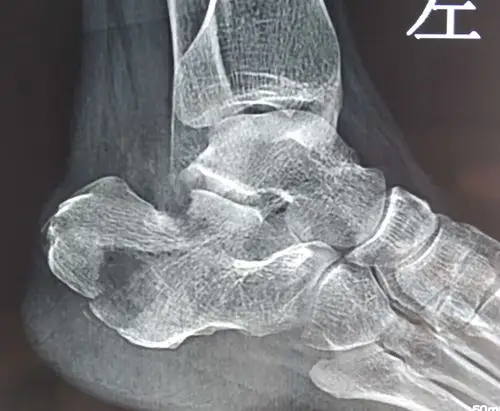

跟骨骨折,46岁

双侧跟骨骨折

微创撬拨复位空心钉固定治疗跟骨骨折

左脚跟骨粉碎性骨折如何冶疗好